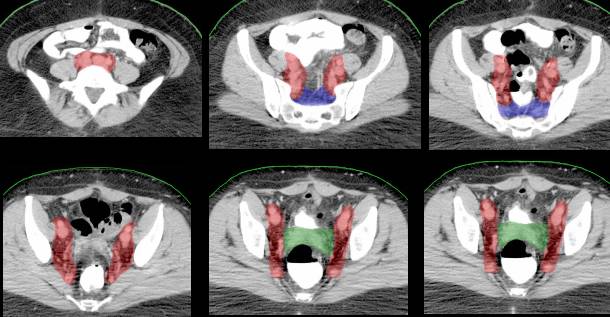

IMRT field (blue) surrounding the cervix cancer (red) and the involved lymph nodes (green) |